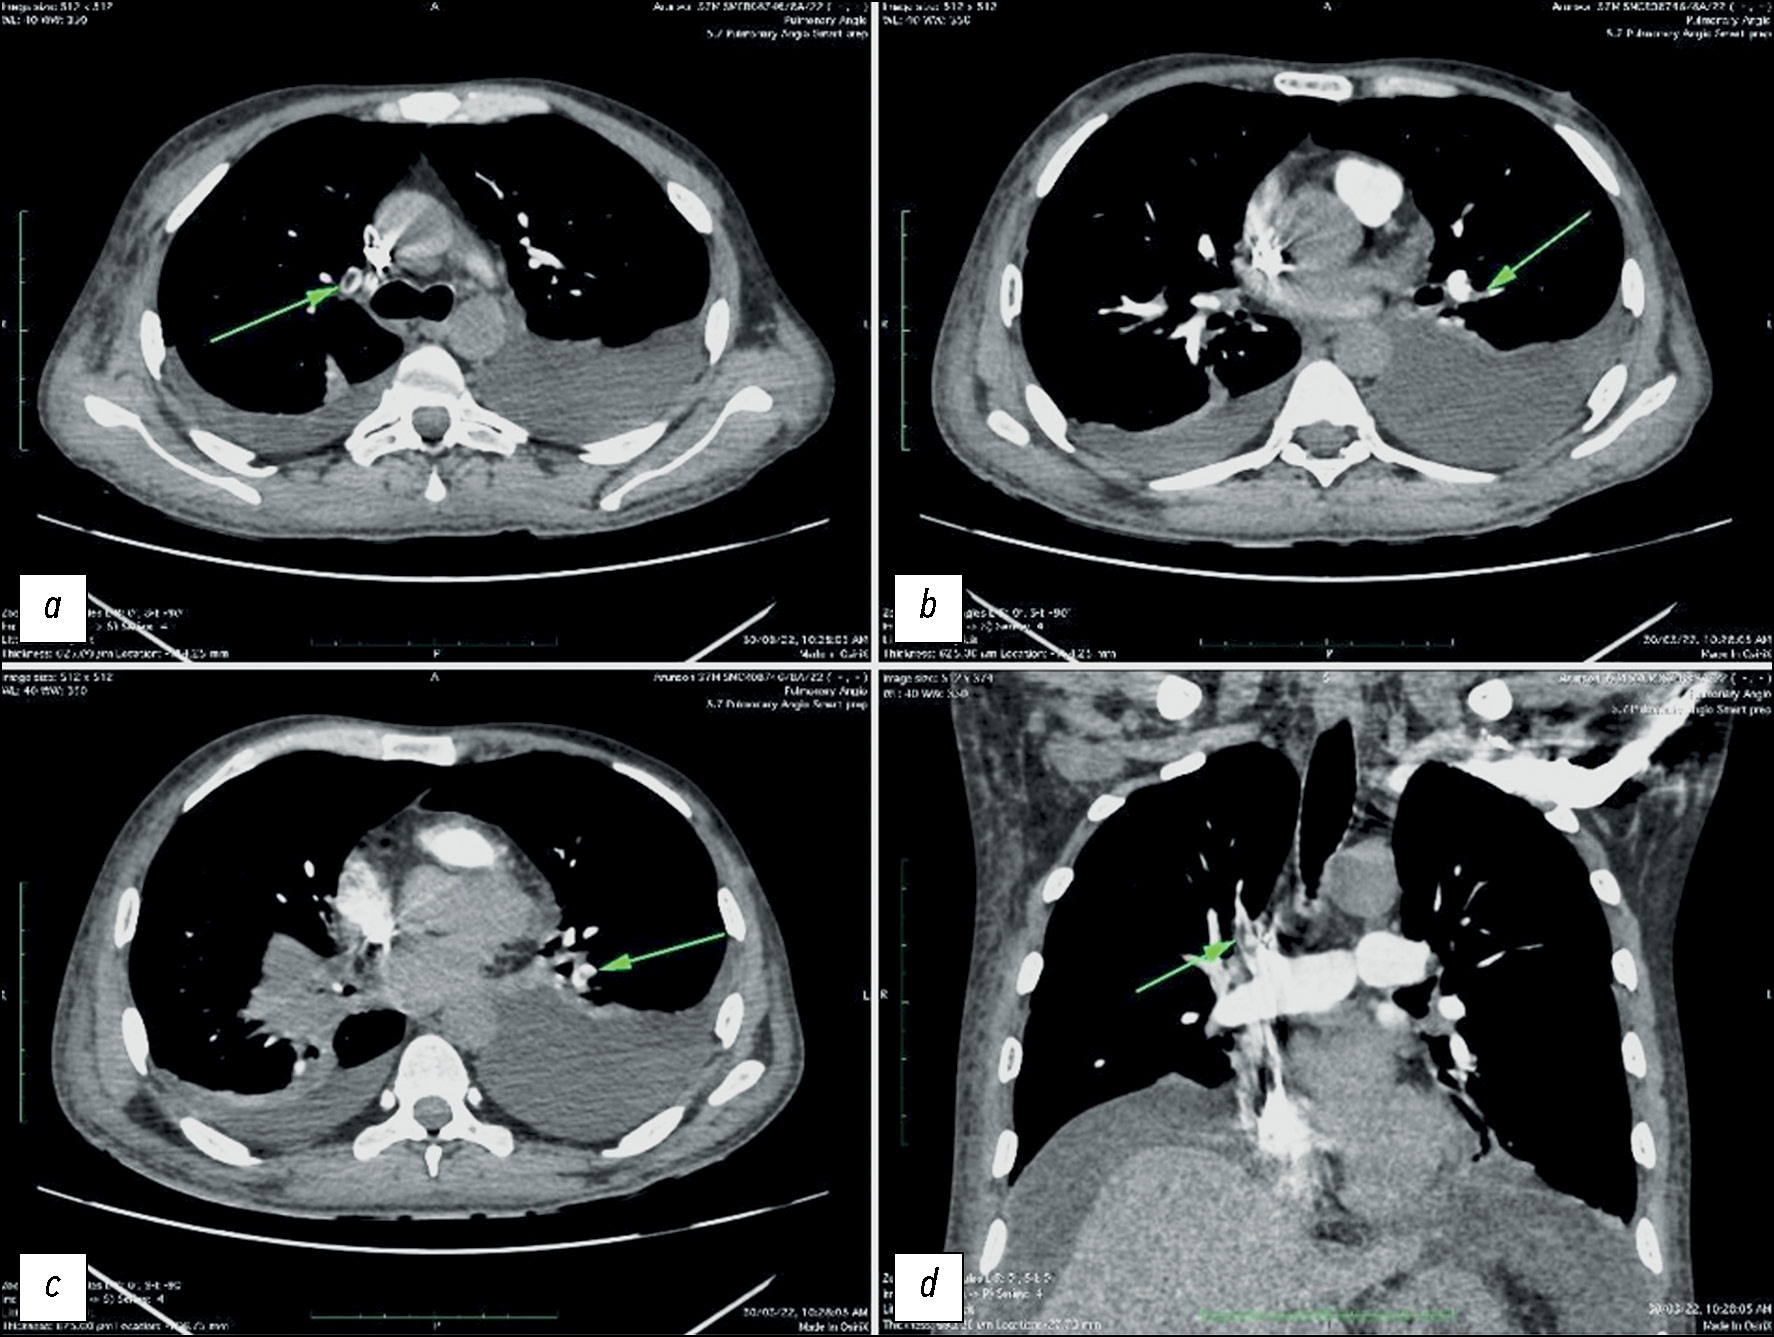

Псевдоаневризма лёгочной артерии у молодого человека с лёгочной гипертензией по данным компьютерной томографической ангиографии

Псевдоаневризмы и аневризмы лёгочной артерии — нечастые нарушения, однако связанные с ними осложнения подчеркивают важность их распознавания. В данной публикации представлен клинический случай пациента 15 лет, который поступил в клинику с жалобами на кровохарканье. При диагностике была обнаружена аневризма артерии левого лёгкого. Результаты последующей компьютерной томографической ангиографии и вмешательства на лёгочных артериях подтвердили наличие аневризмы лёгочной артерии, что позволило предположить, что кровохарканье было вызвано разрывом аневризмы. Вмешательство на лёгочной артерии подтвердило диагноз. Раннее выявление и лечение аневризмы лёгочной артерии имеют решающее значение, особенно у молодых пациентов, так как своевременное вмешательство может предотвратить тяжёлые осложнения и улучшить исход заболевания. Повышение осведомлённости об этих сосудистых нарушениях и их своевременное устранение с помощью соответствующих диагностических мер и вмешательств может помочь медицинским работникам эффективно снизить потенциальные риски, связанные с аневризмами лёгочной артерии, и тем самым улучшить точность их прогноза и качество оказываемой пациентам медицинской помощи.